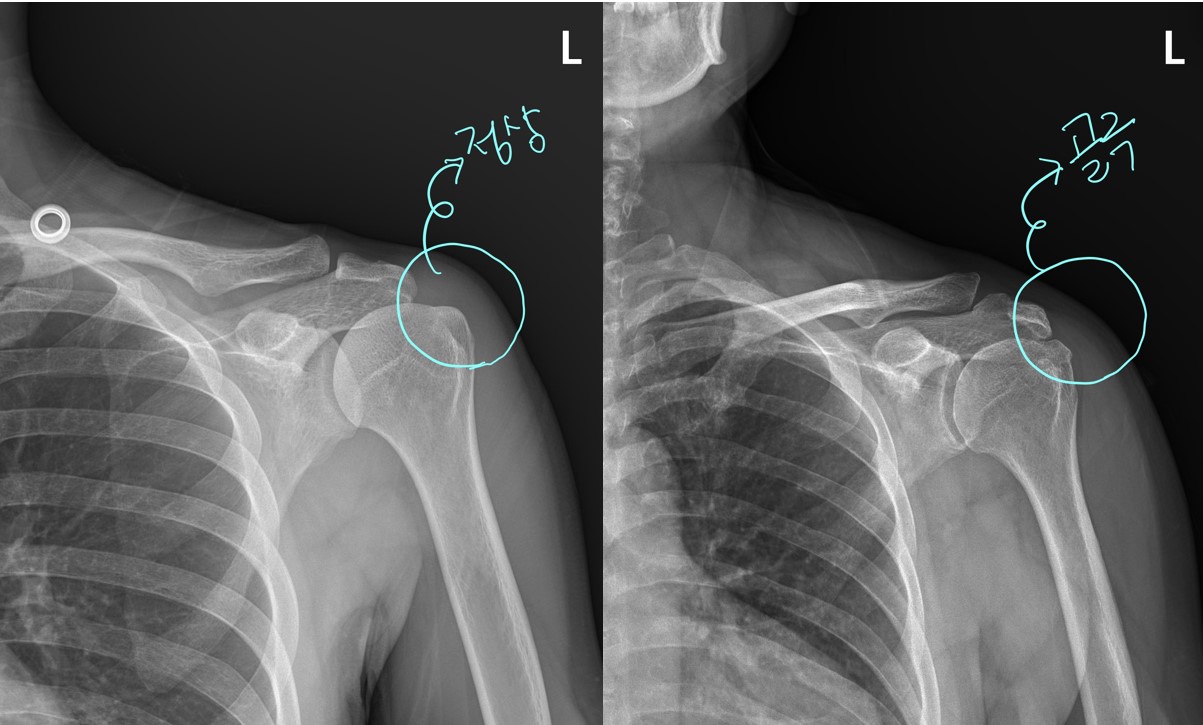

우선 x-ray를 좀 살펴보면..... 이것만 봐도 어깨 상태가 심상치 않음을 느낍니다. 일반적으로 정상적인 X-ray는 위팔뼈의 라인이 둥글둥글하게 부드럽게 넘어가야 하는데 이 환자분의 위팔뼈 부분은 울퉁불퉁하고 뾰족뾰족한 부분이 보입니다.

이걸 '골극'이라고 하는데요... 뼈의 특정 부위에 염증이 반복되거나 그 부위에 뭔가 자극이 되면 뼈가 자라는 것을 말합니다.

아프고 불편한지가 수년이 되었는데 x-ray 상에서 이렇게 골극이 보인다는 것은 뭔가 문제가 상당히 있을것을 추측할 수 있습니다.